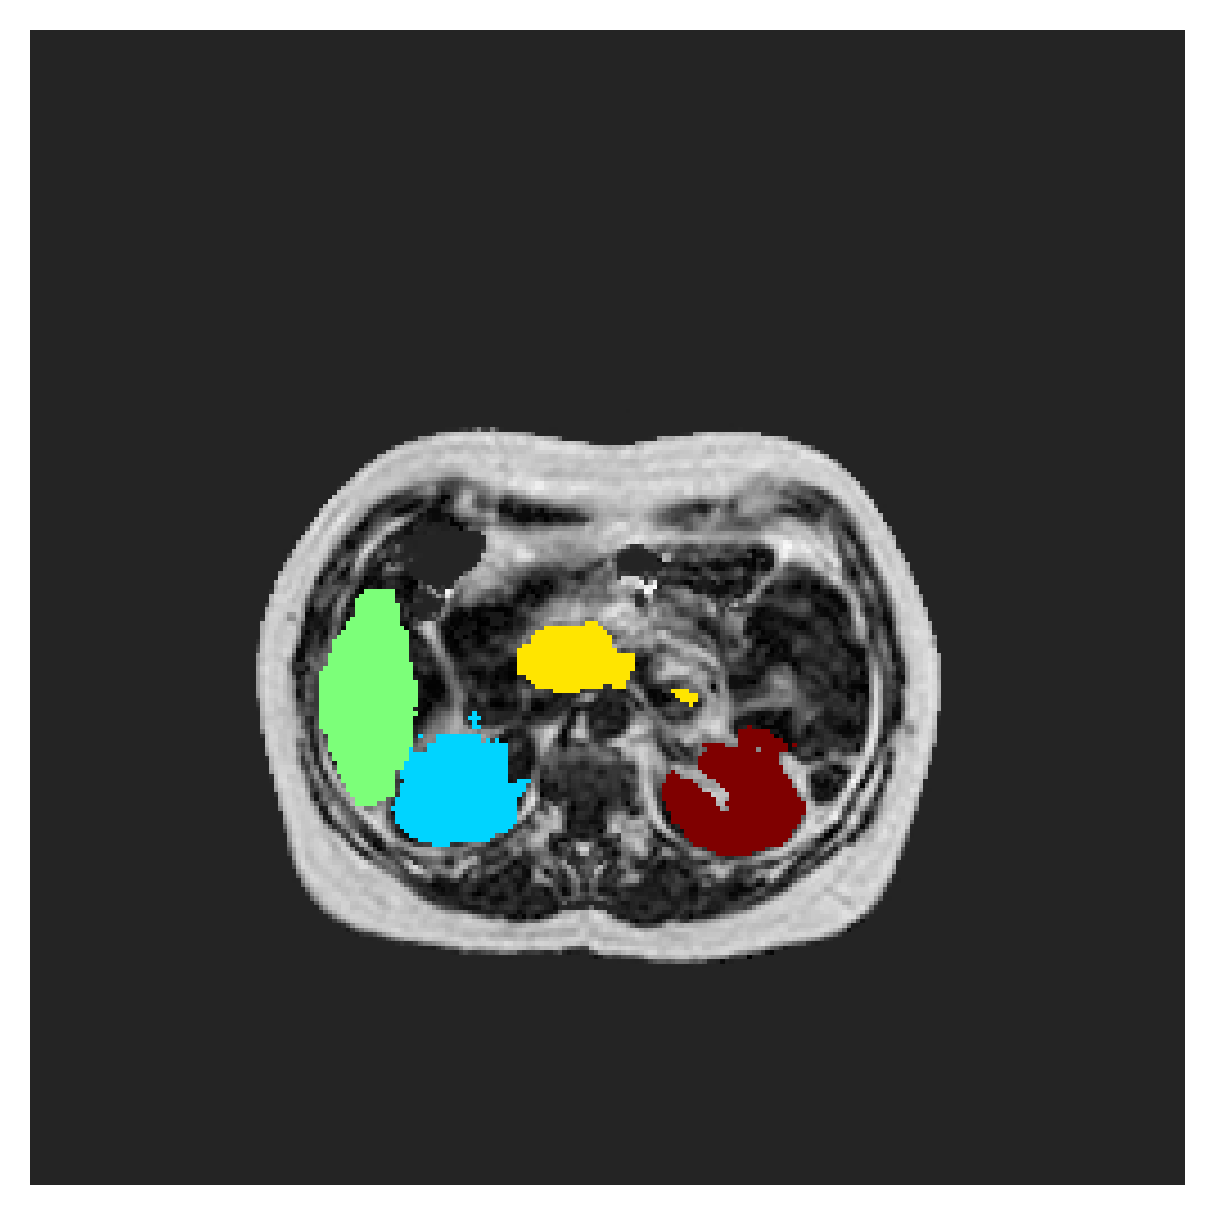

We normalize the volumes and resize the slices to pixels. As the official dataset comes with full annotations, we create a synthetic point ground truth. This is done by first randomly choosing the centers of the point annotations within the class masks, followed by filling an ellipse with axes lengths of and (in pixels) around each center. The intersections of these elliptic discs with the underlying full annotations are then used as our point ground truth. See Figure 2 for an example of the created weak annotation mask. The point annotations are created for every slice, one for each foreground object present in the slice.

The images contain two channels, one for water and one for fat content. For training, we normalize the volumes (per channel) and use 2D slices in the coronal plane, sized . The weak annotations are created synthetically, following the same procedure as described for the ACDC dataset.

In Table 3, the average DSC and HD95 results are shown (both using 2D and 3D distance maps) for the task of abdominal organ segmentation in POEM data (for boxplots see figures 8 and 9). We see that training with and (with distances calculated on 2D slices) performs comparably, while using and produces lower scores in both DSC and HD95 metric. On this dataset, the CRF-loss is able to compete with the boundary loss-based training strategies, even outperforming them on most classes. Most notably, all models trained with boundary loss appear to have a hard time segmenting the liver. We hypothesize this may be due to extremely severe class imbalance, as the liver covers a very large area compared to the rest of the classes. It is thus also more strongly affected by undersegmentations.

5.2.1 Qualitative comparison

In Figure 11 and 12 we show the same random slices in cases of calculating the boundary loss on 2D- and 3D-based distances, respectively. Comparing the two figures again indicates that the intensity-aware distances offer most improvement when calculated in 3D over 2D. The exception here is the MBD, which seems to even slightly degrade for most classes.